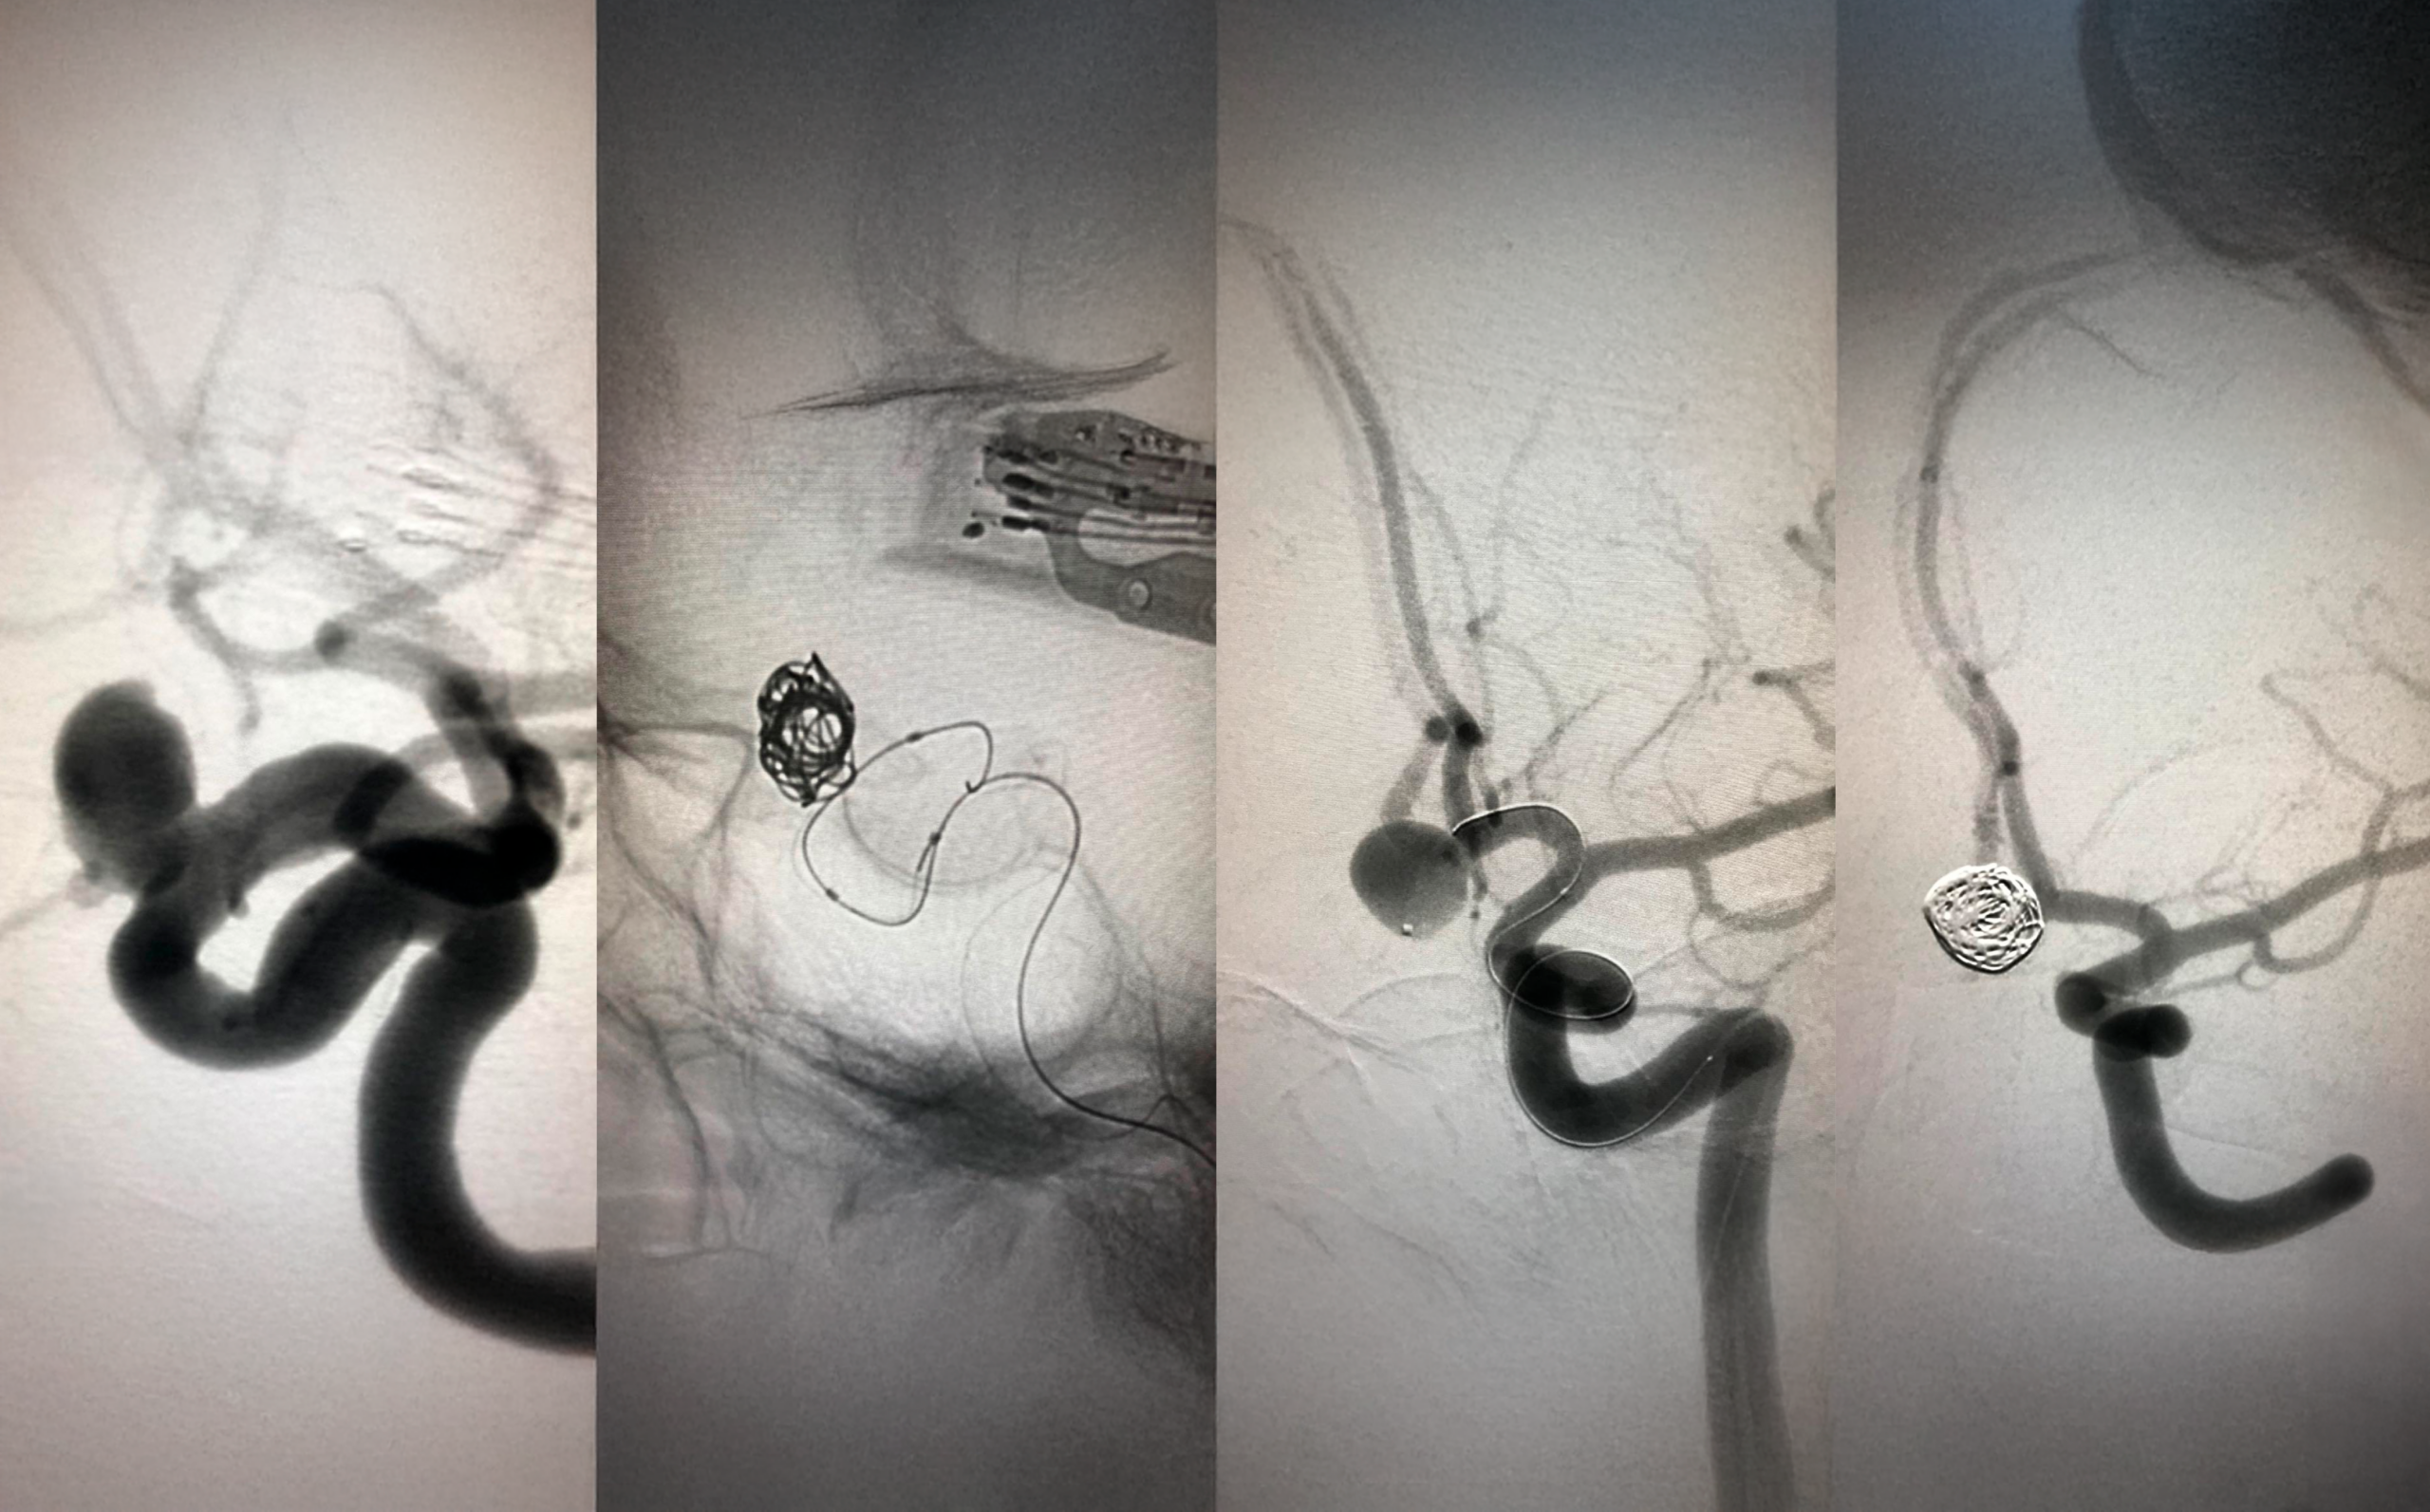

O aneurisma cerebral é uma dilatação localizada no calibre de uma artéria, devido a uma fraqueza na sua parede, principalmente nas bifurcações. Fatores de risco como hipertensão arterial, tabagismo e antecedentes familiares aumentam a chance do aparecimento e rotura dessa malformação arterial. A rotura de um aneurisma cerebral leva ao óbito em 50% dos casos no primeiro mês sem tratamento. A colocação de um clipe metálico no colo do aneurisma por microcirurgia foi o padrão ouro por várias décadas. Mas, a neurocirurgia endovascular tornou-se a terapia de escolha, por ser menos agressiva, com baixa morbidade e alto índice de oclusão do aneurisma.

Serbinenko, em 1974, descreveu a oclusão de aneurismas cerebrais pela colocação de balões por cateterismo. Guglielmi, em 1991, realizou a oclusão de aneurismas com micromolas de platina destacados por eletrólise. Esta técnica se desenvolveu e passou a ser usada de rotina nos maiores centros mundiais. O uso de stents e balões facilitaram a colocação das micromolas em aneurismas de colo (abertura) largo.

Atualmente, existem várias opções de materiais para a oclusão de aneurismas com segurança, as micromolas foram deixando de ser as mais utilizadas. Os diversores de fluxo são materiais parecidos com stents, mas bem mais flexíveis e com a malha bem mais fechada. Eles são implantados frequentemente nos aneurismas de diferentes artérias, principalmente os de artéria carótida interna. Temos muitos pacientes tratados com esse material. O Web é como uma pequena gaiolinha, com a malha semelhante ao diversor de fluxo, que é colocado no interior do aneurisma para a sua oclusão, A sua principal indicação são os aneurismas de colo largo em bifurcações arteriais.